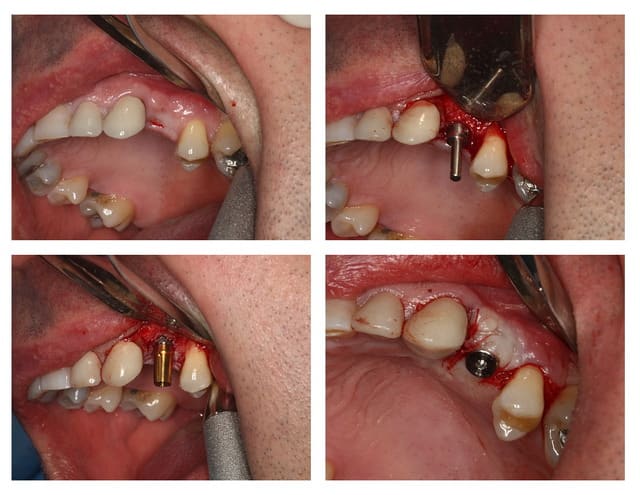

extract récente implant + Vitalos

moi, ce qui m'interpelle, c'est le choix de l'EEI qui t'oblige à te laisser embarquer dans une alvéole qui ne te donnera pas forcement le meilleur axe ni le meilleur centrage

pourquoi ce choix?

> moi, ce qui m'interpelle, c'est le choix de l'EEI qui t'oblige à te laisser

> embarquer dans une alvéole qui ne te donnera pas forcement le meilleur axe ni le

> meilleur centrage

> pourquoi ce choix?

pas forcément l'os où je voulais